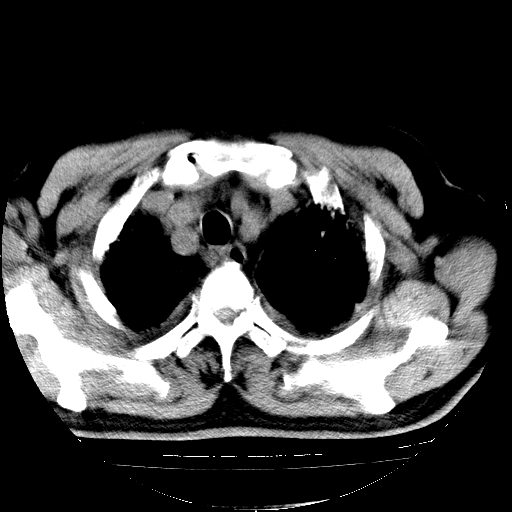

男,68岁,咳嗽、胸闷、发烧三天,查体:双肺散在湿罗音。

首先考虑特发型肺间质纤维化;两侧少量胸腔积液。

依据:1、两肺广泛条索状、网格状、蜂窝状改变。